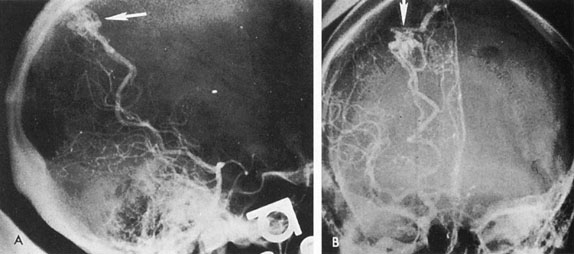

The therapy for AVMs has been reviewed elsewhere.91–93 The preferred treatment remains complete surgical excision of the malformation. However, significant advances in endovascular and radiosurgical techniques have resulted in a marked increase in the use of multimodal, staged approaches to AVM treatment. A variety of intravascular techniques use embolization91 with materials such as particles of polyvinyl alcohol (PVA), platinum coils, and injection of liquid N-butyl-cyanoacrylate (NBCA) adhesive (Fig. 11). Complications of intravascular embolotherapy include vessel perforation by the catheter, migration of embolic materials, and infarction and hemorrhage of normal brain.

Fig. 11. Embolization of middle cerebral vessels that supply occipital lobe arteriovenous malformation (AVM). The patient had a subarachnoid and intraparenchymal hemorrhage that produced a left homonymous field defect. A: Right carotid arteriogram demonstrates contribution via posterior communicating artery to a right occipital lobe AVM. B: Vertebral injection. The arrow points to the enlarged right posterior cerebral artery that is a major feeder of the AVM. C: Right carotid arteriogram during glue embolization procedure. The arrow points to a catheter as it traverses the segment seen in (B). The catheter was advanced via the internal carotid artery but is positioned far posteriorly. D: Upper branches to the AVM now are occluded, with residual low-flow vascularization via the middle cerebral artery. E: Skull film showing radiopaque glue within the AVM and blood vessels previously supplying it. The patient had a persistent visual field defect but greatly reduced headache and no persistence of subjective bruit. (Courtesy of Dr. Joseph Horton.)